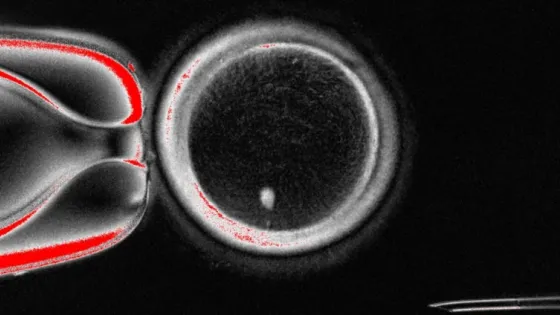

Обложка: Изображение из статьи. Яйцеклетка с перенесенным соматическим ядром и видимым веретеном деления перед ИКСИ Mitalipov laboratory